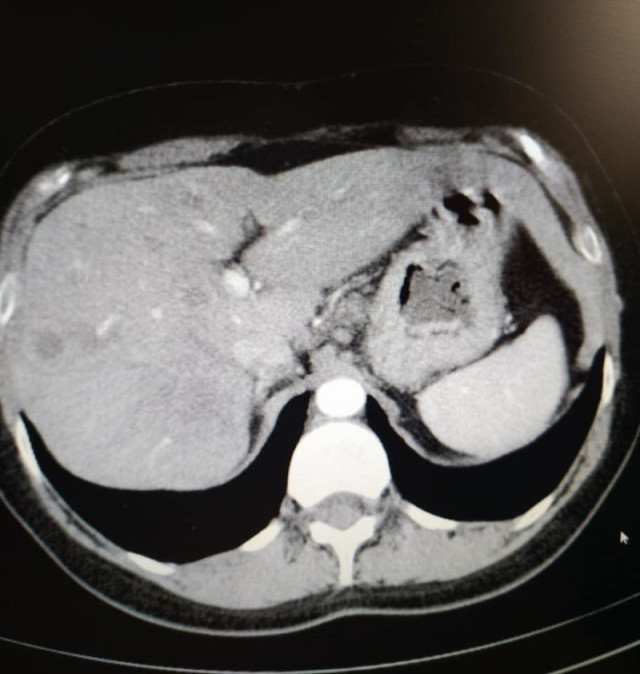

"У мене метастази, 4 стадія, але постійна від початку лікування позитивна динаміка. З 5 пухлин різних за розмірами в печінці, залишилася одна 12 на 10мм, яка була на початку 50мм. На першому фото печінки видно плями темні-це вони,метастази,а на другому фото теперішній стан. Це дуже успішне лікування. Ще трішки і я надіюсь і ця пухлина теж зникне", – розповіла вона.